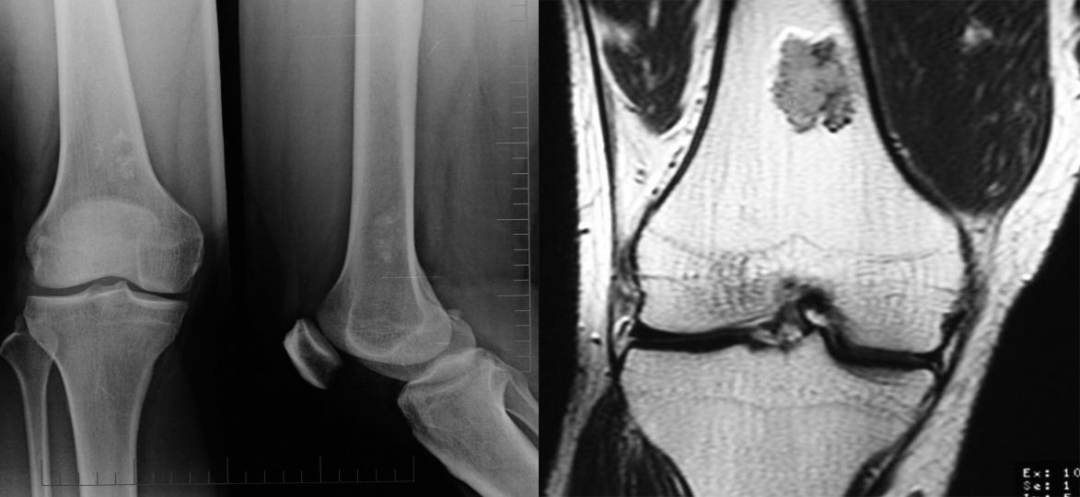

①骨巨细胞瘤:是一种潜在的恶性肿瘤。多发生于骺板愈合后的长管骨骨端,紧邻骨性关节面偏心性生长,横向膨胀性生长明显,呈皂泡样改变。

(注:女,20 岁,左侧桡骨干骺端见界限清楚、扩张性、偏心性、透明性病变,在桡骨骨骺处有内部分隔,延伸至干骺端并毗邻骨皮质。)

(注:患者一年后复查,可见膨胀性病变范围增加,现在延伸到整个桡骨下端,病灶主要以横向生长为主。)